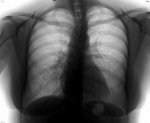

Ненормальные непрокаченные* ОГК...

Любителям смотреть с телефона-планшета, проку здесь нету. Поборникам бокового стандарта достанется мало. Клиника (в части случаев и лаборатория) воспаления лёгочного. Парень в шапке. Женский пол подойдёт. На этой ветке тонкие изменения - типа, бронхита бродят... Кто читает их бронхопневмонией, тоже прав - КТологи подтвердят. Кто заключает, когда изменений с кулак, здесь норму прочтёт - предвосхищаю!

• мужчина, 29 лет